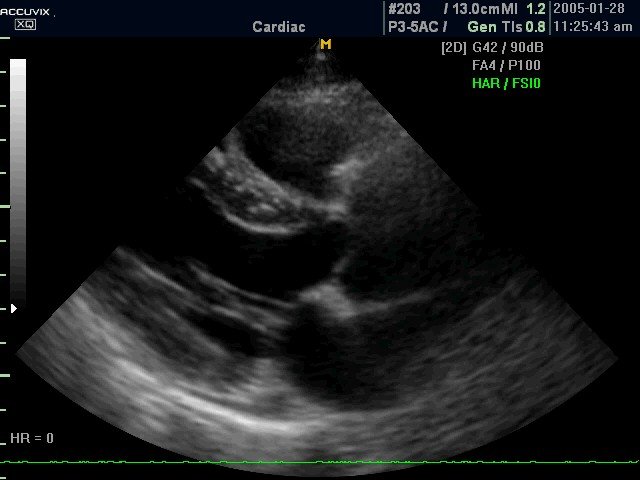

УЗИ сканер Accuvix-XQ (Medison, снят с производства)

Accuvix XQ - ультразвуковой сканер компании Medison экспертного класса (версия XQ) с цветным, двунаправленным энергетическим, тканевым, импульсным и непрерывноволновым допплером, трехмерное УЗИ в реальном времени (3D обычными и 4D объемными датчиками).

Высочайшая разрешающая способность, новые технологии формирования трехмерного изображения, мультислайсинг и стресс-эхо - рекомендация применения сканера Accuvix XQ ведущими исследовательскими институтами и кардиоцентрами.

- Пакет кардиологических исследований:

- в 2D-режиме рассчитываются значения таких параметров, как объем по методу Симпсона (Simpson), объем по площади и длине, двумерные характеристики (например, фракция выброса левого желудочка) и масса левого желудочка;

- в M-режиме вычисляются значения параметров для левого желудочка, аорты и левого предсердия, митрального клапана, а также частота сердечных сокращений. - Пакет расчетов параметров сосудов: вычисления объёмного кровотока, процента стеноза, индекса сопротивления (RI), пульсационного индекса (PI) и др.

Фазированный датчик P 2-5AC/15

Кардиология и транскраниальные исследования у взрослых.

Фазированный датчик P 2-5AC/19